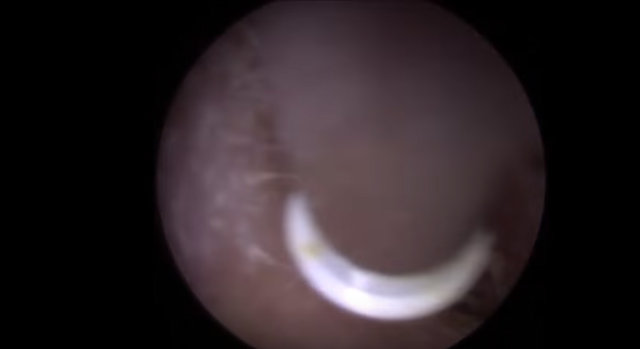

Kulağından 22 tane nesne çıkarılan adam hayrete düşürdü. İşin garip yanı ise kulağının içinden çıkan şeylerin işitme cihazı olmasıydı...